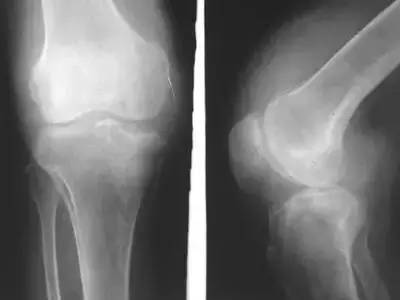

走出来的滑膜炎!前不久,杭州的刘先生想通过暴走减肥,每天走的步数都在15000以上,没想到,不到一星期,就患上了膝关节滑膜炎!医生说,刘先生是走得太多了!属于过度运动,已经伤害到了身体!

日行2万步,膝关节积液!张阿姨今年50多岁,平时爱好锻炼身体的她,经常到附近公园散步,基本上每天两万步打底。没想到,这种追求健康的方式给她带来大麻烦。正是因为走路太多,对膝盖产生了损伤,时间长了,原本应该起到润滑关节作用的关节腔液越来越多,这才形成了积液。